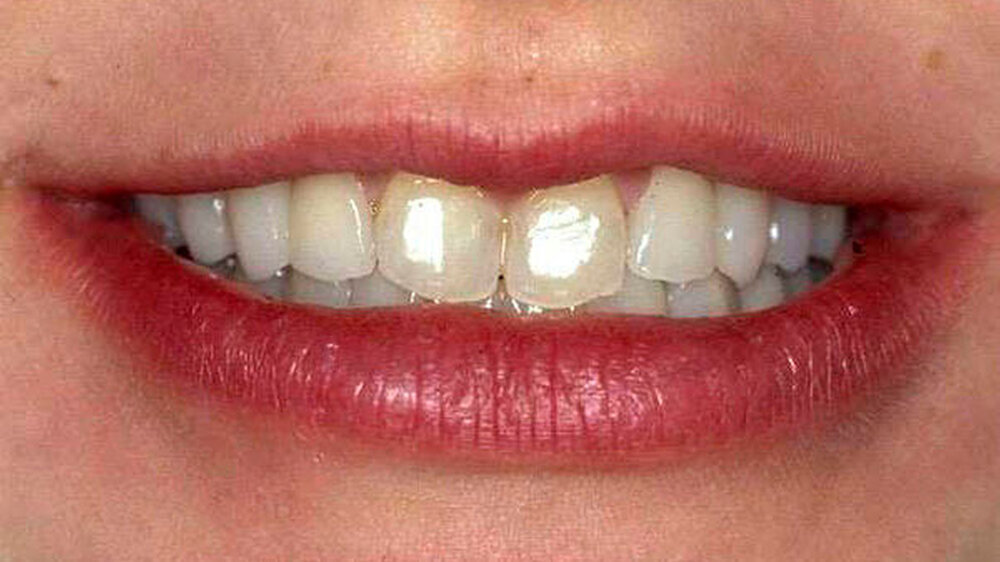

Den Geschwistern wurden dann im Alter von 18 beziehungsweise 20 Jahren insgesamt 43 Implantate gesetzt, die auch 14 Jahre nach dem Eingriff noch komplikationslos für einen festen Biss, eine Verbesserung der Gesichtsästhetik und damit für ein gutes Selbstwertgefühl sorgen. Eine der drei Schwestern berichtete auf der Jahrespressekonferenz der Deutschen Gesellschaft für Mund-, Kiefer- und Gesichtschirurgie (DGMKG) anlässlich des großen 65. Kongresses in Stuttgart über ihre Geschichte mit Happy End.

Die definitive Prothetik wurde vier Monate später eingesetzt. Seither erfolgen regelmäßige Verlaufskontrollen und wichtige Hygienemaßnahmen. Auf den aktuellen Panoramaschichtaufnahmen, die bis zu 14 Jahre nach Abschluss der Behandlung erfolgten, stellt sich ein stabiles periimplantäres Knochenniveau bei allen drei Patientinnen dar. Die klinischen Untersuchungsparameter an sämtlichen Implantaten waren unauffällig. Sowohl in der Funktion als auch in der Ästhetik ist ein Langzeiterfolg zu verzeichnen.